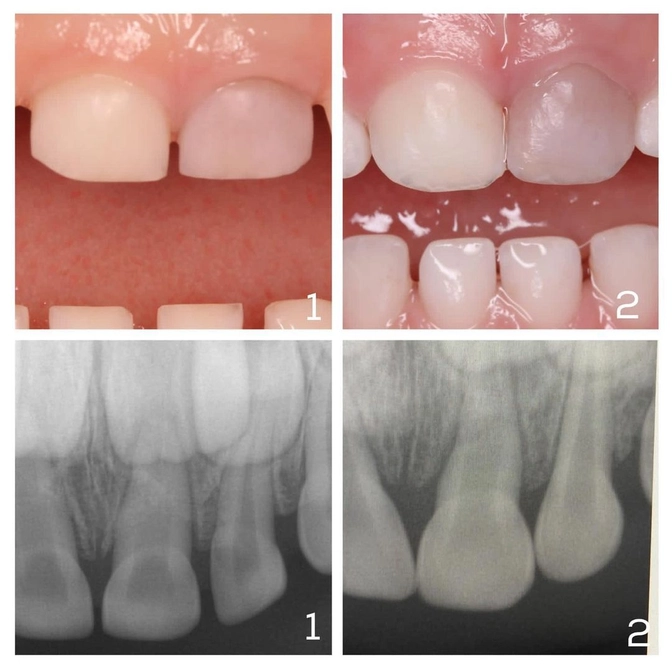

1. Фото и снимок под номер 1 — пациент детского стоматолога Алёны Долгалёвой.

Малышу 4 года.

Он ударился центральным резцом (6.1), в результате чего тот посерел.

В этом случае врач проводит визуальный и инструментальный осмотр, делает снимок, чтобы оценить состояние корня.

Серость зуба — не повод для удаления.

Зуб меняется в цвете из-за кровоизлияния в пульпу, но если не произошло отрыва сосудисто-нервного пучка и корень цел, то постепенно цвет зуба вернется к естественному.

У этого пациента всё обошлось.

Зуб оставляем под динамическое наблюдение, и заодно провели профессиональную гигиену.

2. Второй пациент (фото и снимок под номером 2) пришел к детскому стоматологу Светлане Кожемякиной.

Ему 3 года, и практически идентичная травма.

Ушиб центрального резца 6.1.

Спустя 10 дней зуб посерел.

При постукивании ощущается боль, есть небольшая подвижность.

Чтобы дать заключение, врачу требуется снимок.

Что видим?

Из-за травмы началась резорбция корня (рассасывание) — а это уже показание к удалению зуба.